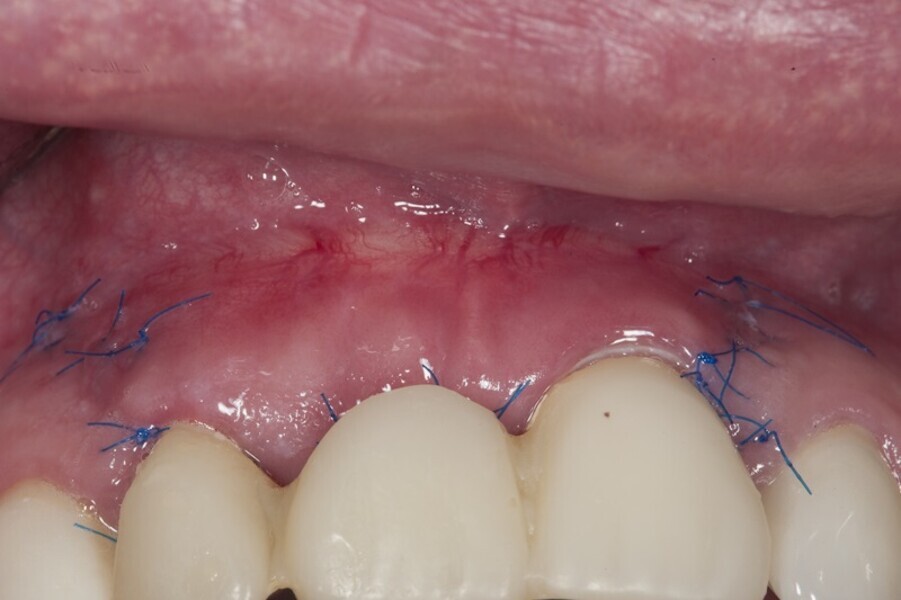

Biomodulacja laserem Nd:YAG z użyciem głowicy Genova®